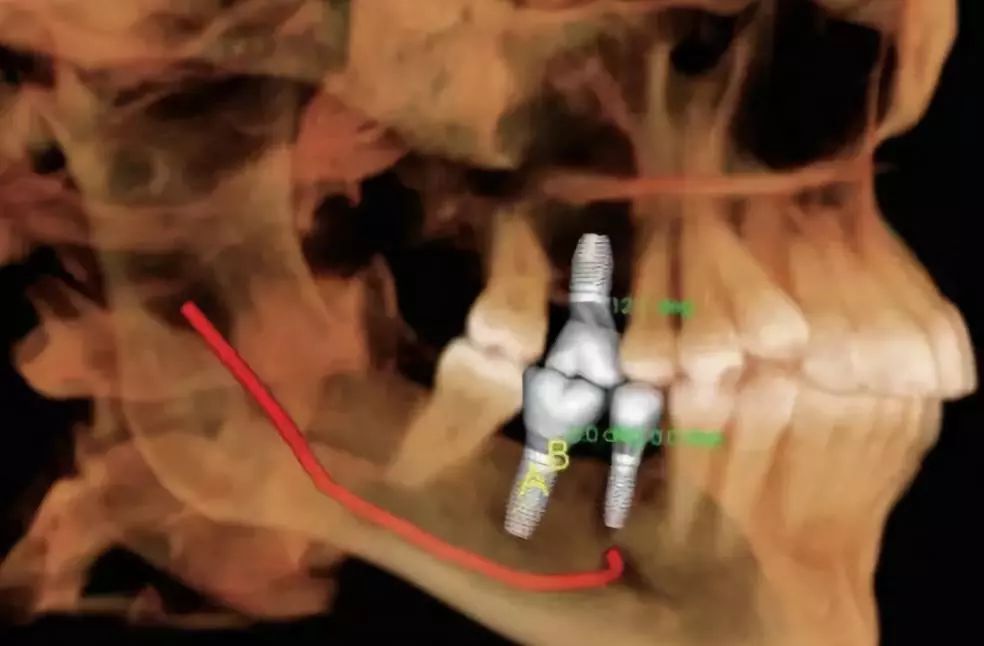

口腔CT是圍繞人體的一段容積螺旋式的采集數(shù)據(jù)。口腔CT與常規(guī)CT的本質(zhì)區(qū)別在于前者獲得的是三維信息,而后者獲得的是二維信息??谇籆T機(jī)提高了掃描速度,掃描覆蓋面廣,無間隙采集容積數(shù)據(jù),便于各種方式、各種角度的影像重建,且可以任意地、回顧性重建。視野選擇與圖像合成方面,口腔CT機(jī)比常規(guī)CT有著明顯的優(yōu)勢。它的空間分辨率高,對下頜骨、下頜神經(jīng)管、顳下頜關(guān)節(jié)解剖結(jié)構(gòu)、牙齒根管系統(tǒng)成像質(zhì)量更好。以下介紹三維口腔CT機(jī)的臨床應(yīng)用特點是什么?

4.神經(jīng)管定位功能

利用口腔CT機(jī)特有的神經(jīng)管著色功能,可以清楚標(biāo)識下頜神經(jīng)管與相鄰的重要解剖結(jié)構(gòu)的相鄰關(guān)系。如下頜阻生智齒拔出時,觀測神經(jīng)管與牙根的距離。